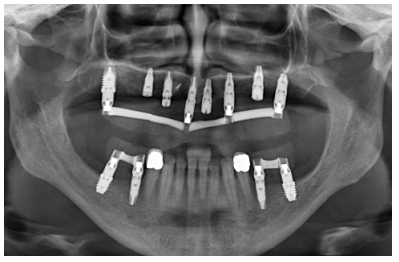

Para iniciar la fase de diagnóstico se realiza una radiografía panorámica que nos de una idea del estado general de ambos maxilares para iniciar el plan de tratamiento. En ella se ve como existe aparentemente altura en el reborde maxilar tanto a nivel anterior como posterior y un nervio dentario bajo en la mandíbula que nos permite tener una mayor cresta ósea residual disponible para la inserción de los implantes (Figura 3).

Posteriormente, se procede a la realización de un Cone-beam dental que ofrece una visión más exacta del tipo de rehabilitación implantológica que se pueda plantear. En los cortes correspondientes al maxilar superior, se observan zonas donde puede realizarse la inserción directa de los implantes como las correspondientes a 16 y la zona del incisivo central de este cuadrante (Figuras 4-5) o en el segundo cuadrante el área de 27. En cambio, en la zona correspondiente a los dientes 21 y 23 existe una atrofia horizontal importante, con una anchura ósea residual de aproximadamente 3,5 mm en la zona media de la cresta, con una ampliación en el área más basal de la misma y conservación de ambas corticales. Esto hace que se opte por una técnica de Split de cresta, en este caso en dos fases para poder lograr una mayor anchura final y corregir la inclinación del implante final todo lo posible para lograr una estética en la prótesis final adecuada (Figura 6).

suficiente volumen óseo en anchura y altura para la inserción directa de un implante en esta posición.

En las zonas correspondientes a los dientes 11 y 13 la atrofia horizontal es todavía más marcada. No existe hueso trabecular separando las dos corticales (vestibular y palatina) y la anchura es menor a 2 mm en algunas zonas lo que hace que en esta área se planifiquen injertos en bloque. En la mandíbula se planifican implantes cortos mediante inserción directa, y la zona correspondiente a la rama mandibular será el área donante para los injertos en bloque.

Cuatro meses después de la cirugía inicial de regeneración del maxilar se lleva a cabo un nuevo Cone-beam dental, en el que se planifica la siguiente fase de la cirugía en función de la ganancia ósea que se ha logrado con los injertos en bloque y la técnica de Split en dos fases. En las imágenes podemos observar como en las zonas de máxima atrofia, donde se colocan los bloques se ha logrado una anchura que triplica la inicial (Figuras 19 y 20). En la apertura del colgajo se observa como las imágenes del TAC de planificación se corresponden con la realidad, y además que la zona tratada mediante Split en dos fases ha logrado también una anchura de cresta que ahora permite la retirada de los implantes transicionales y la inserción de nuevos implantes en esta posición, con una mejor situación de partida y eje para la confección posterior de la prótesis (Figuras 21-22). Se procede a la inserción de los implantes y se realiza una prótesis provisional de carga progresiva apoyada en los implantes colocados en la primera fase quirúrgica. De este modo, la paciente puede tener una prótesis fija sobre implantes que servirá para ir dando forma a los provisionales en cuanto a estética y función de cara a la prótesis definitiva (Figuras 23-24).